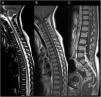

Afectación de las raíces de la cauda equina y la médula espinal, corte sagital. Hiperintensidad extensa en la espina dorsal anterior en secuencia T2, desde el segmento cervical al cono medular (flechas en A). Tras la administración de contraste, la imagen sagital en secuencia T1 mostró captación en las raíces ventrales de la cauda equina (flechas en C) sin captación en la mayoría de la médula espinal (B).